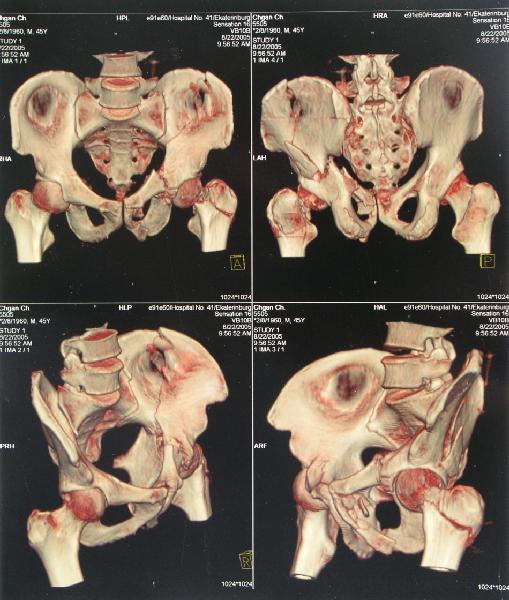

Наш больной пока обследуется, сделали сегодня КТ наконец-то.

Today CT was performed.

Сегодня КТ сделали.

I'd probably start with femoral open reduction and internal fixation initially, and then reassess potential acetabular repair.